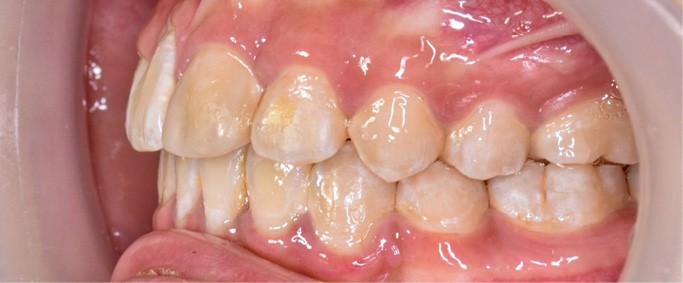

Une patiente âgée de 12 ans se présente en consultation, motivée par la position de son incisive centrale maxillaire, décrite comme « en avant », marquée par une dyschromie et une mobilité de grade 2 selon Muhlemann. L’examen clinique montre l’absence de 23 sur l’arcade, une dysharmonie dents-arcade marquée, un surplomb accentué, et une déviation des milieux inter-incisifs, conséquence du comblement spontané de l’espace de 23. L’ensemble s’inscrit dans un contexte de Classe I d’Angle molaire. L’orthopantomogramme révèle l’inclusion de 23, associée à une résorption radiculaire étendue aux deux tiers de 21. La 22 ne présente aucune altération visible.

La patiente, de profil normodivergent, présente une Classe I squelettique sans troubles fonctionnels (fig. 1-8).